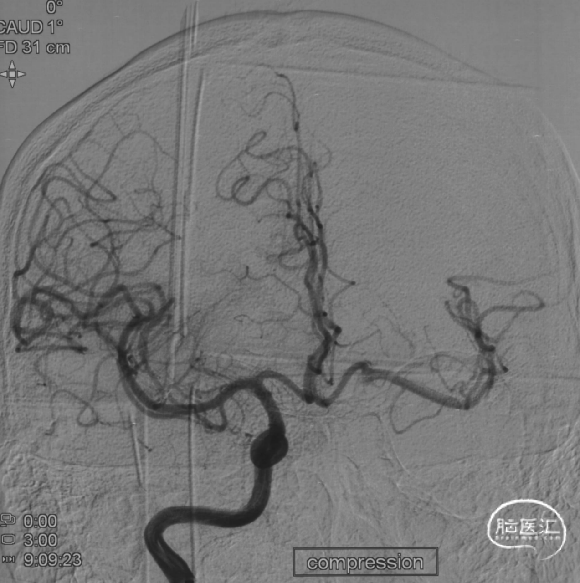

压颈试验:前交通开放

Fastrack微导管到位